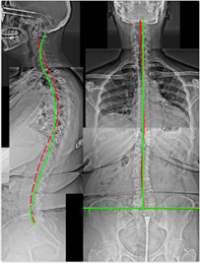

Case 4 — 83yo Female: Unable to Straighten Up

Figure 4. Severe Scoliosis, Severe Thoracolumbar Kyphosis, Anterior Head Translation, Right Lateral-Listhesis L4 on L5. The lateral listhesis — a serious structural finding — was entirely unknown prior to imaging.